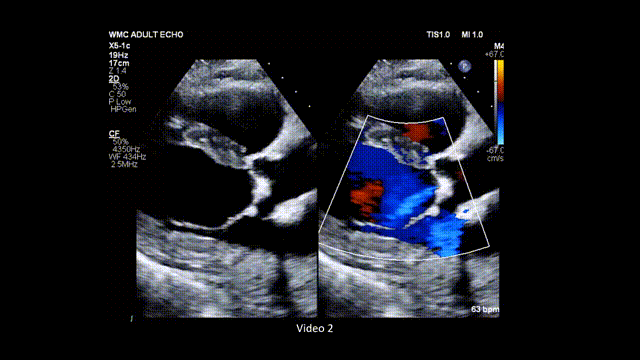

2、 在胸骨旁长轴切面放大(zoom)主动脉瓣(AV)和二尖瓣结构,分别采用普通二维和彩色多普勒模式进行评估(图3,视频2)。

图3. 胸骨旁长轴切面放大图像(普通二维和彩色多普勒对比)

胸骨旁长轴切面下主动脉瓣的放大图像,分别展示使用普通二维和彩色多普勒的情况。缩写同图2。

视频2. 胸骨旁长轴切面应用彩色多普勒(彩色与二维灰阶对比模式),评估主动脉瓣是否存在反流及主动脉瓣狭窄时典型的彩色镶嵌血流模式。